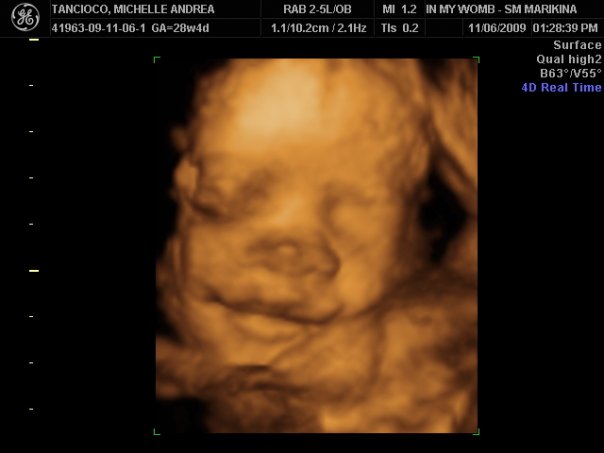

Hanz And Calleigh S World 2009